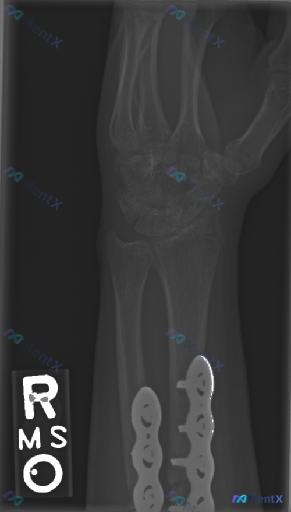

- 背景:右腕关节桡骨远端及尺骨远端骨折术后复查

- 本次检查:右腕关节侧位X光片

- 骨骼与内固定:桡骨远端及尺骨远端可见金属钢板及螺钉内固定装置;骨折部位皮质对位对线良好,未见新发明显断裂透亮线或台阶感;腕骨序列排列基本完整,各腕骨形态无明显塌陷或粉碎,未见明确腕骨骨折线。

- 关节对位:桡腕关节、腕中关节、下尺桡关节对位良好,月骨与桡骨、头状骨对位正常,无明显脱位/半脱位,无“倒置茶杯”征或腕骨间分离;桡骨纵轴与第三掌骨纵轴对齐大致平直。

- 骨质与关节间隙:骨小梁结构连续,未见明显广泛骨质疏松;骨质密度均匀,无明显骨质破坏、溶骨/成骨肿瘤征象,无骨囊肿或死骨;内固定周围骨质无明显异常硬化或透亮区;桡腕及腕骨间关节间隙宽度尚可,无明显不对称狭窄,关节边缘光滑,无明显骨赘或退行性骨关节炎改变。

- 软组织:骨周软组织轮廓清晰,未见明显弥漫性肿胀或脂肪垫移位。

目前表现为右腕关节骨折内固定术后较好的愈合状态,内固定在位、固定牢靠,未见明确急性脱位、骨折不愈合或严重退行性变征象。